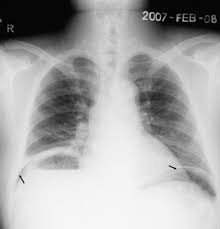

3. Your patient is a 82 year old male who presented with a sudden onset of abdominal pain. He is diffusely tender with involuntary guarding. He has hypoactive bowel sounds. He has had some nausea and vomiting. His vital signs are as follows Temp 97.9, O2 Sat 99% RR-20 Pulse 99, BP 143/76. An upright chest x ray has been ordered prior to you seeing the patient by the triage nurse. Take a look at the X Ray below.

Given the above data, what is the best management option for this patient now?

A. Send the patient for a 3 dose oral and IV contrast CT scan of the Abdomen and pelvis

B. Order the patient some Morphine 4 mg IV and Zofran 4 mg IV.

C. Place an NG tube in the patient

D. Call for a general surgery consult right now.